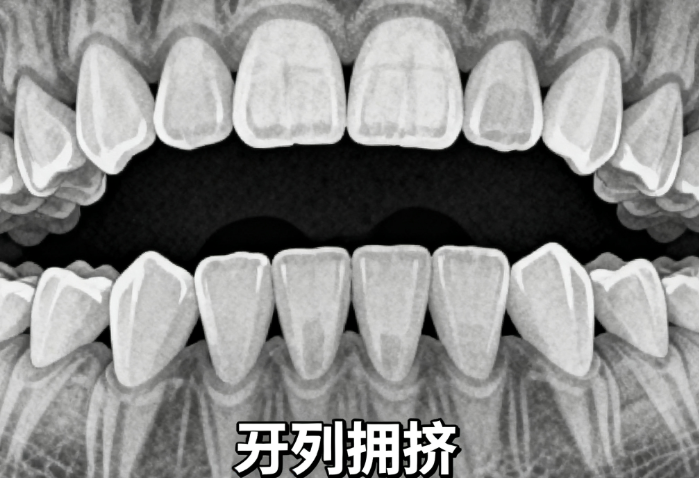

牙齿拥挤度:拥挤较重,可能需要先拔牙

咬合关系:上下牙咬合不正,需要调整